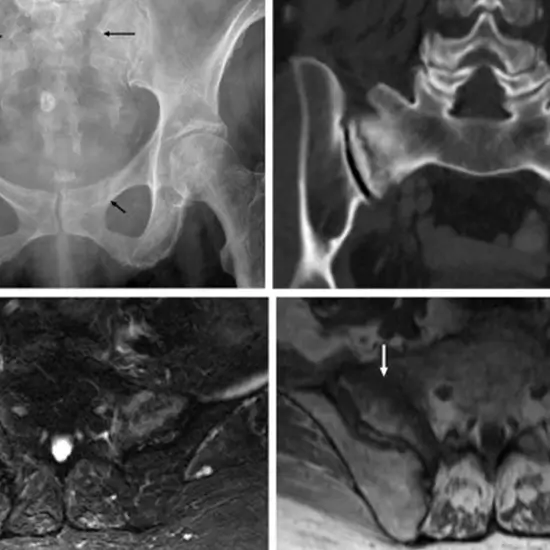

An MRI screening of the Bilateral SI joint visualizes the joint and surrounding tissues located between the ileum and sacral bones of the pelvis.

MRI (Magnetic Resonance Imaging) screening arm is a non-invasive medical diagnostic tool used to obtain detailed images of the bilateral SI joint and the related tissue. MRI Screening bilateral SI joint is used to show abnormalities like fractures, injuries, and strains of the bilateral SI joint.